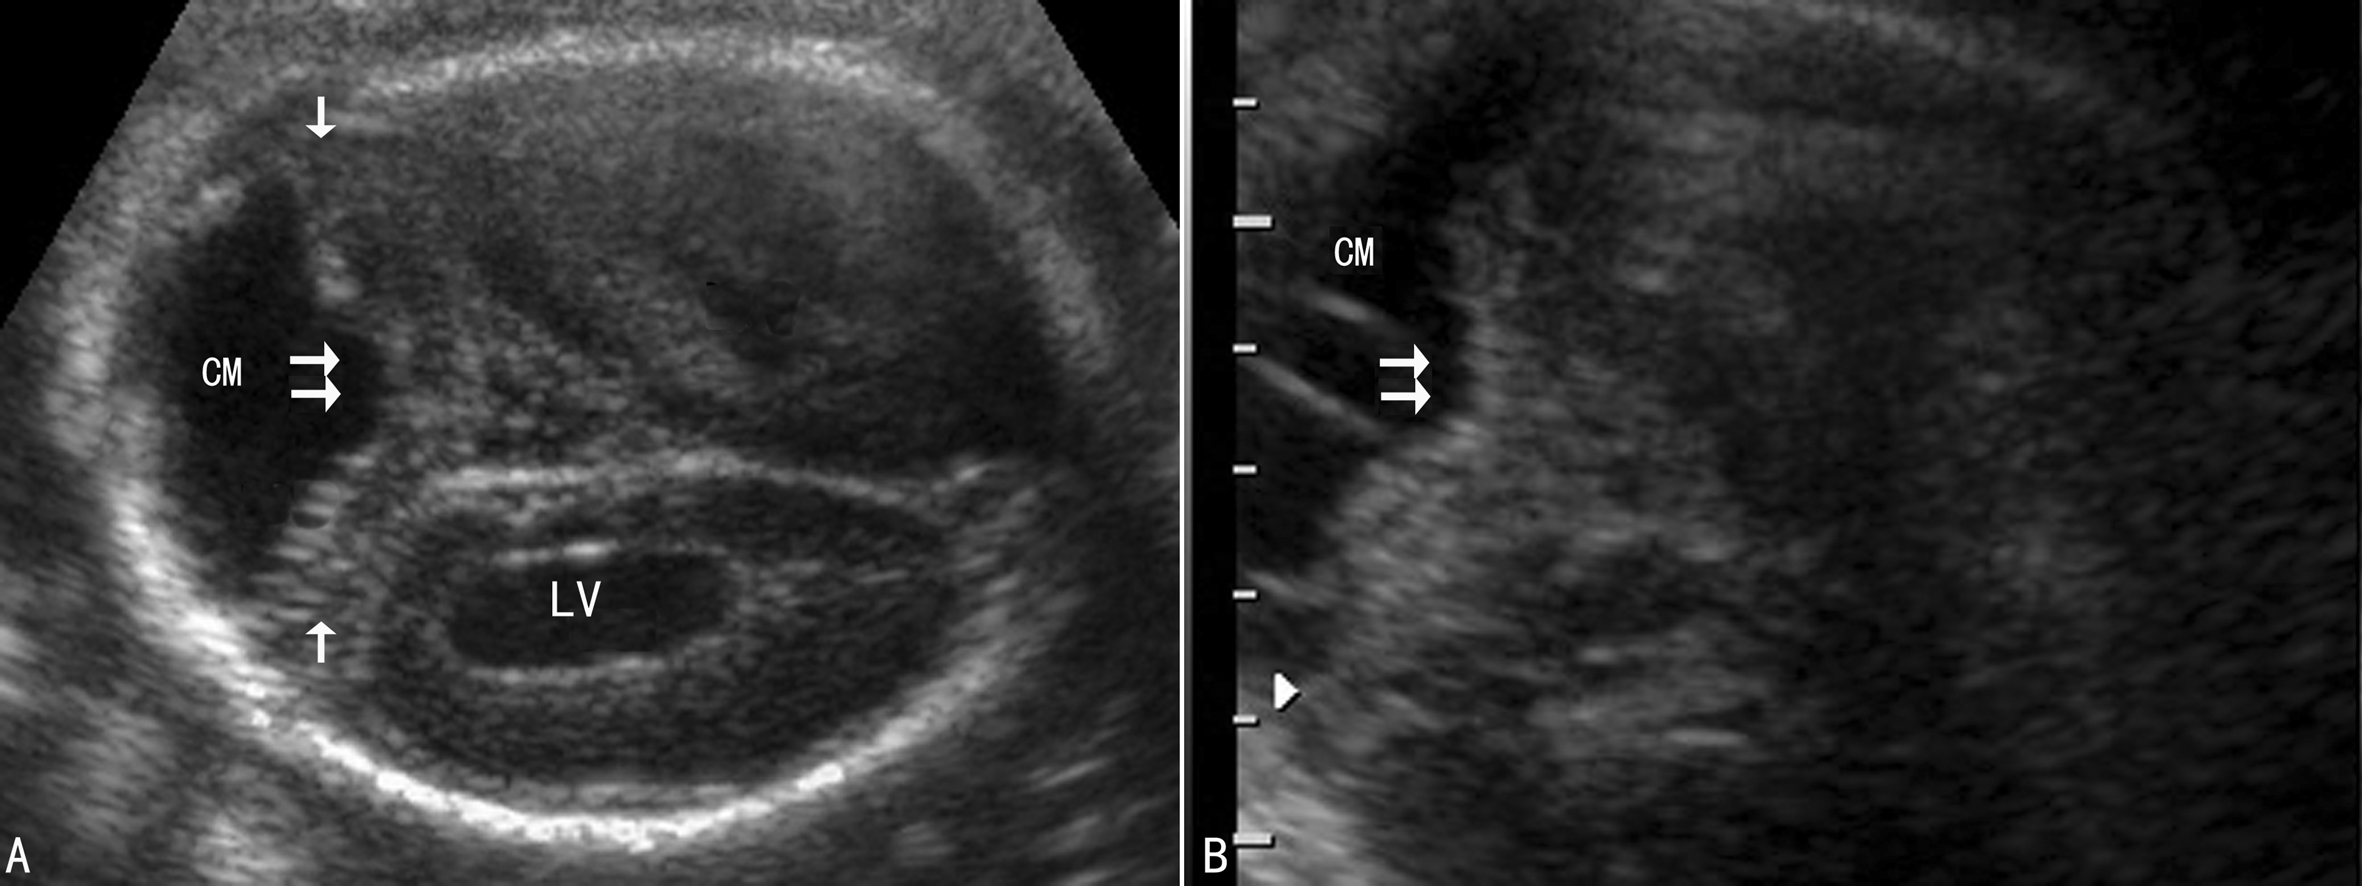

产前超声检查主要针对AM Ⅱ型。胎儿头部超声显像检查90%可有脑室扩张,双顶径小于孕龄,柠檬状头型,中线偏移、脑内结构紊乱,第四脑室和小脑幕、延髓移位,后颅窝池消失,小脑变小弯曲呈“香蕉状”、蚓部疝入枕骨大孔;脊柱超声显像检查显示椎弓骨化中心断裂、缺失、异常弯曲、后凸或侧突,局部显示脊膜膨出或脊髓脊膜膨出、脊柱裂等。如果在胎头枕部或额部、顶部显示颅骨缺损和脑膨出,则提示为AM Ⅲ型。

脊膜膨出或脊髓脊膜膨出、脊柱裂等是诊断AMⅡ型的必备条件。一般认为正是因为脊柱裂的存在,椎管压力低于颅脑压力,脑脊液从椎管流出,引起颅内压力减低、双侧颞骨内陷,形成了胎头的“柠檬头”征;第四脑室、小脑幕和延髓后移,后颅窝池消失,小脑变形呈“香蕉样”改变,小脑蚓部疝入枕骨大孔。